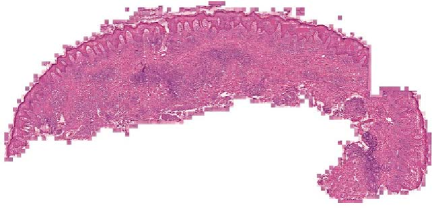

We demonstrate our WSI creation workflow on Leishmaniasis cases, as shown in Figures 1 and 4. An expert pathologist reviewed the cases and annotated granulomas as well as LD bodies on the stitched images and our generated images in Figure 4. To show generalizability of our approach, we also show results on core biopsies of breast, duodenum, stomach, liver, and lymph nodes (Figure 5).

| Breast | Duodenum | stomach | liver | lymph node | |||||

Limitations. Our current model results in significant artifacts at the boundary of the tissue. We will address these and the square artifacts at the borders more rigorously using bi-direction feature fusion GANs [13]. In this work, we used just one microscope which was the cheapest-yet-clinical grade microscope available on market (in developing regions). In the future, we will compare our stitching results on microscopes from different vendors with different resolution cameras. We will also explore using smartphone cameras to acquire videos rather than microscope cameras. We currently require pathologists to pause between frames (ideally with > 50% overlap) to get the best-quality results. In the future, we will explore ways to handle stitching even from faster videos with minimal overlaps. We will also extend our stitching platform to immunohistochemistry-stained images where manual cell counting is tedious and more advanced deep learning approaches can play a critical role in more accurate, objective, reproducible, and faster protein expression quantification. Finally, we will develop deep learning algorithms for detecting granulomas and LD bodies specific to Leishmaniasis.